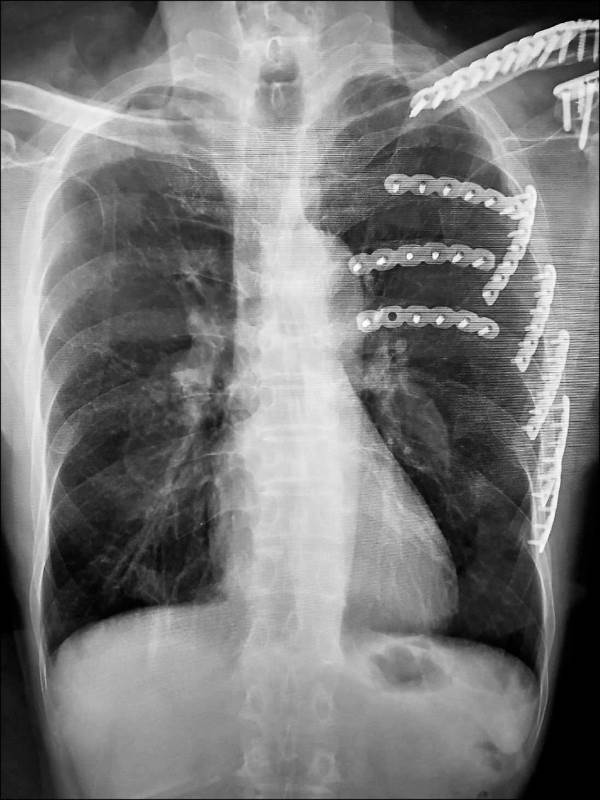

臺中一名70歲陳姓老翁日前遭遇嚴重交通事故,左側第3到第7根肋骨全數斷裂,還出現胸壁挫傷跟血胸狀況,幾乎無法正常呼吸。他被緊急送往國軍臺中總醫院急救,醫療團隊準備為他進行「胸腔鏡輔助肋骨骨折復位矯正鋼板內固定手術」,沒想到術前檢查電腦斷層時,胸腔外科主任謝志明竟在影像中發現更可怕的東西。

3個月後陳先生回診追蹤肋骨復原狀況,謝醫師發現那處病灶依舊存在,立刻安排他接受第2次「胸腔鏡微創手術」將病灶切除。病理化驗結果證實醫師的判斷沒錯,陳先生確實罹患肺腺癌第1期。謝醫師解釋,一般胸部X光很難偵測到1公分以下的微小病變,許多肺癌病患確診時病情已經相當嚴重。